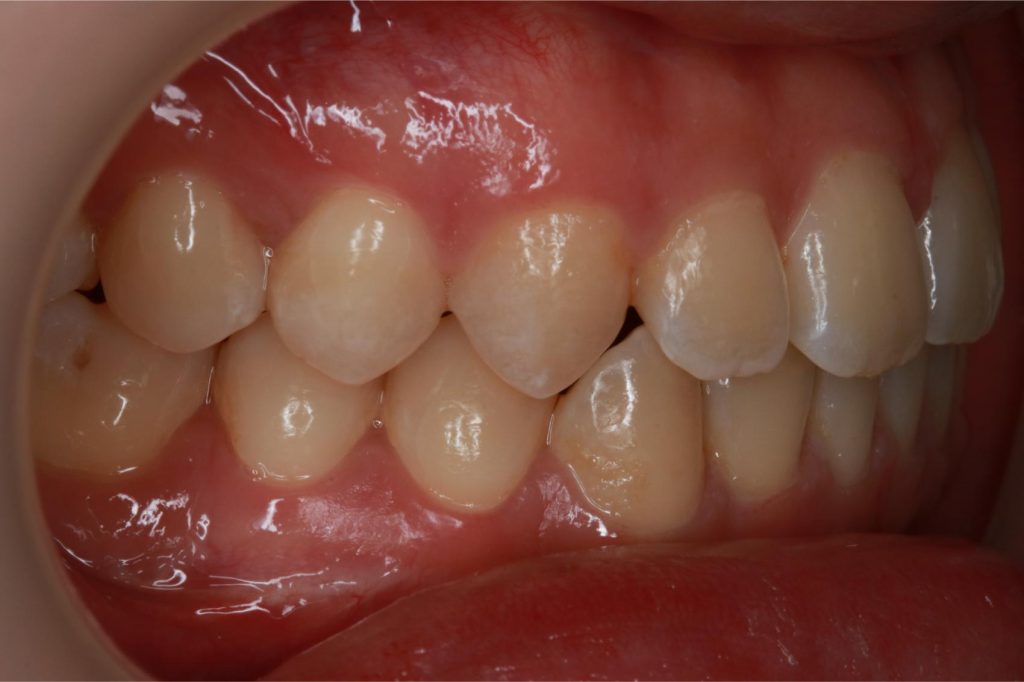

Before and After Images